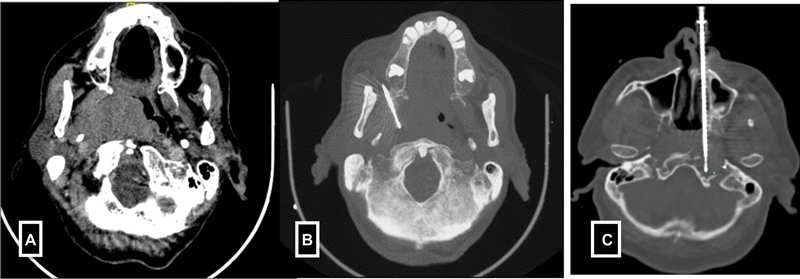

F)Head and neck lesions-Deep seated head and neck biopsies are most commonly performed under CT guidance. Various approaches such as subzygomatic, retromandibular, paramaxillary and submastoid, transoral and posterior approaches are commonly used.[9] In contrast, the biopsies of superficial organs such as lymph node, submental, parotid glands, and thyroid gland lesions are done under USG guidance ([Fig. 4]).

| Figure 4:(A-B) Paramaxiiary approach for parapharyngeal mass biopsy. (C) Trans nasal approach for petrous mass biopsy.

| Figure 4:(A-B) Paramaxiiary approach for parapharyngeal mass biopsy. (C) Trans nasal approach for petrous mass biopsy.